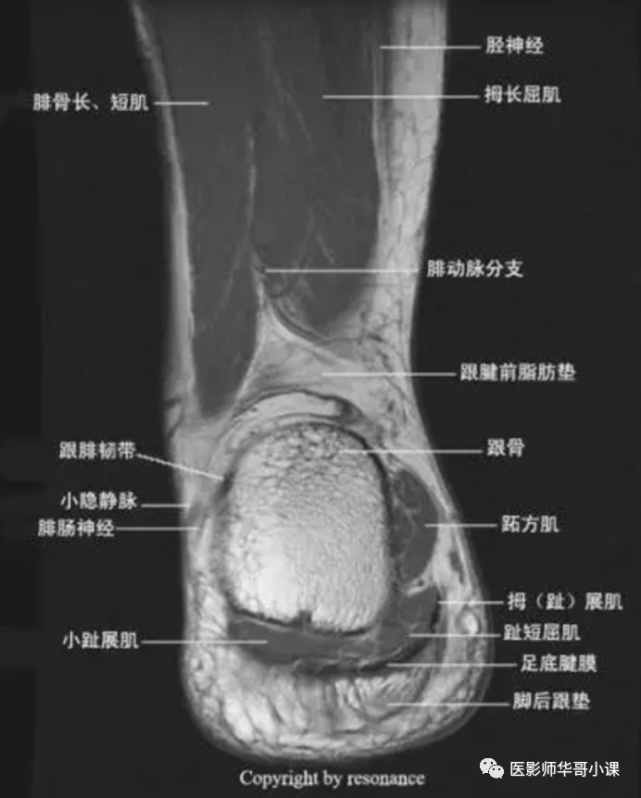

【高清mri图】踝关节磁共振mri解剖

踝关节磁共振解剖图